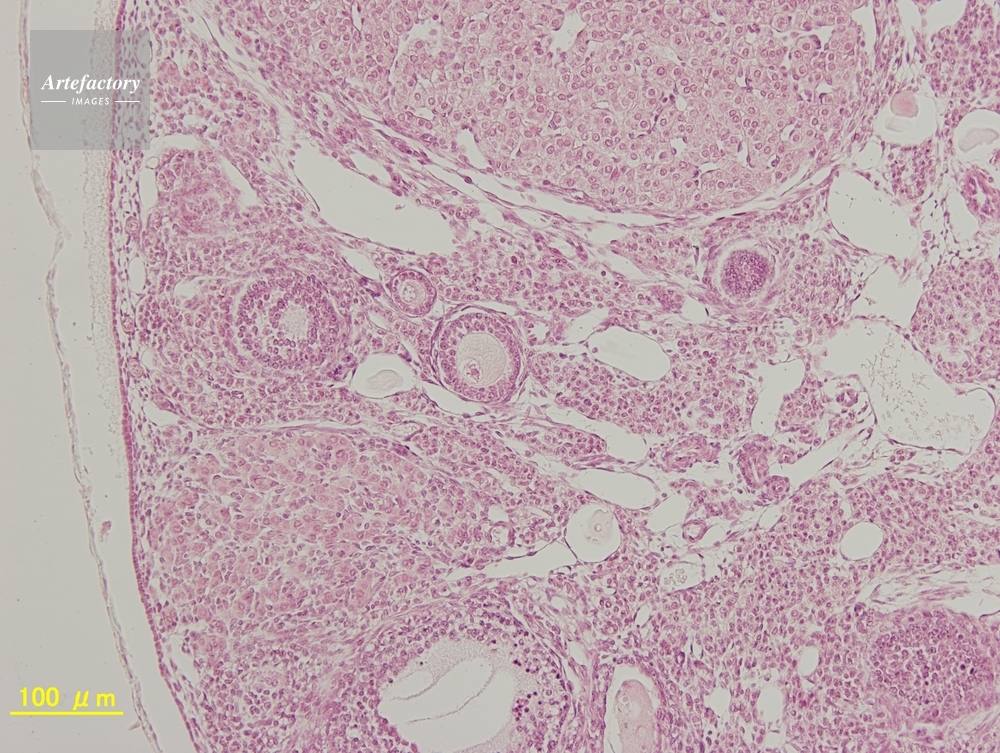

| 作品タイトル | マウス,卵巣 | モデルリリース | なし | |

| 作家 | OLYMPUS CORPORATION Technolab | プロパティリリース | なし | |